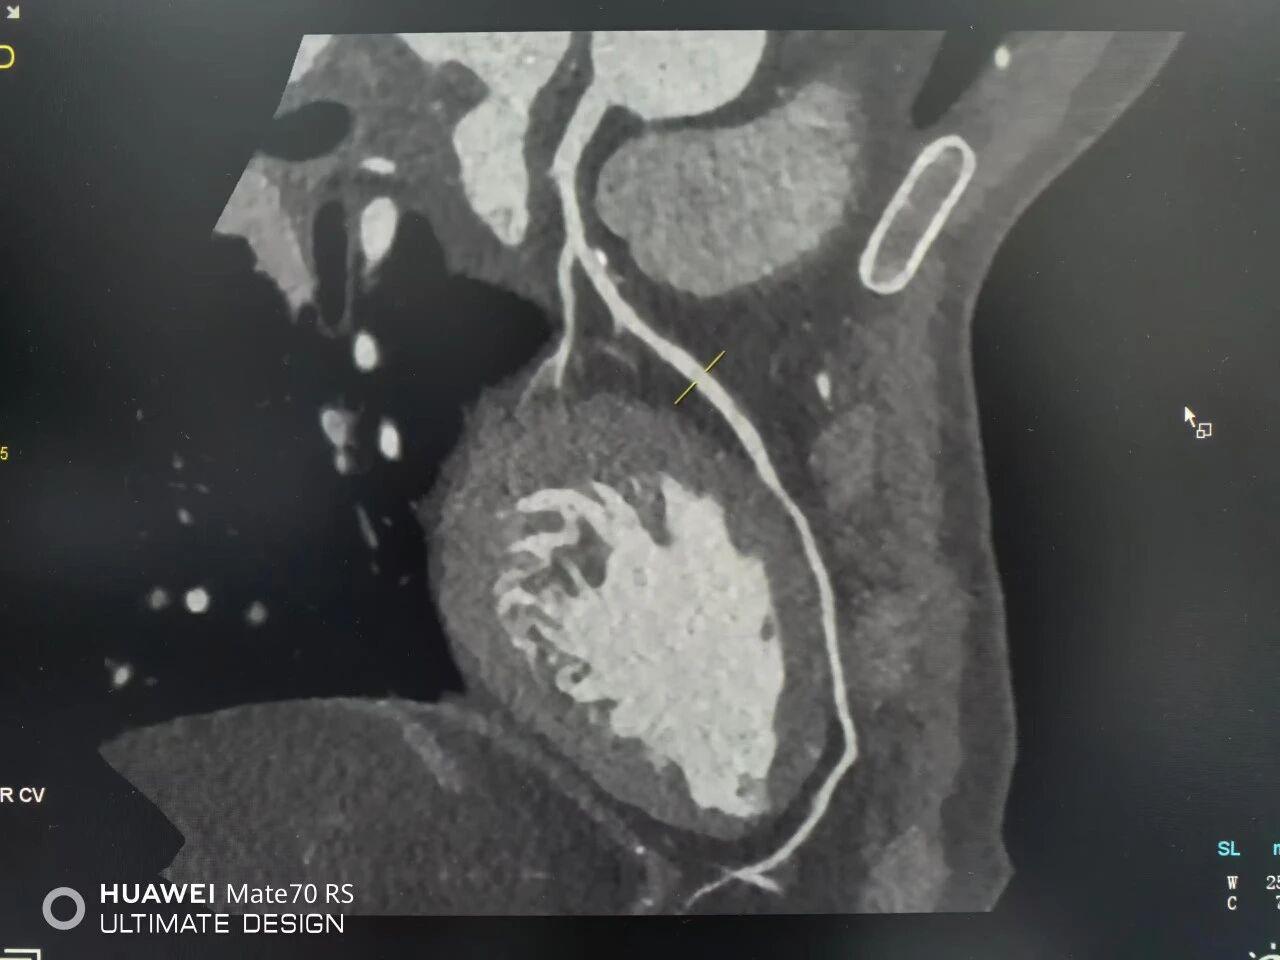

冠心病的本质是冠状动脉血管壁上形成了斑块,导致血管狭窄或堵塞。双源CT的诊断价值不仅在于“看清”血管有多窄,更在于“看透”斑块的性质。

凭借其高达0.24毫米的空间分辨率,这台设备能够:

精准评估狭窄程度:清晰显示冠状动脉的管腔形态,准确判断有无狭窄、狭窄部位和严重程度,其诊断准确性在众多研究中已被证实可与有创造影相媲美 。

识别“危险斑块”:它不仅能看到钙化的硬斑块,更能精准识别危险性更高的“软斑块”(或称“易损斑块”)。这类斑块像“不定时炸弹”,一旦破裂就可能引发急性心肌梗死。通过双源CT的双能量成像技术,医生可以对斑块成分进行分析,为临床制定治疗方案、评估未来风险提供关键依据 。

评估支架与搭桥术后情况:对于已经接受过介入治疗或搭桥手术的患者,双源CT可以无创、清晰地显示支架内有无再狭窄、搭桥血管是否通畅。